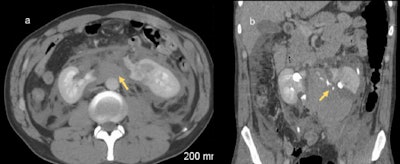

imaging (d) and (e), extravasation of contrast material from the collecting system of the lower pole can be seen. This patient subsequently underwent left nephrectomy.

In cases of penetrating trauma, preliminary noncontrast CT images may be of benefit in identifying and distinguishing extravasation from foreign bodies. If there is suspicion of an injury to the collecting system based on the initial scan, a delayed or excretory phase should be performed after 10 to 20 minutes. Injuries to the collecting system may be indicated on the initial scan by evidence of a laceration that appears to extend to the collecting system or by the presence of perinephric free fluid. Delayed-phase images also are useful in evaluating vascular injuries, such as active bleeding and pseudoaneurysm, the researchers noted.